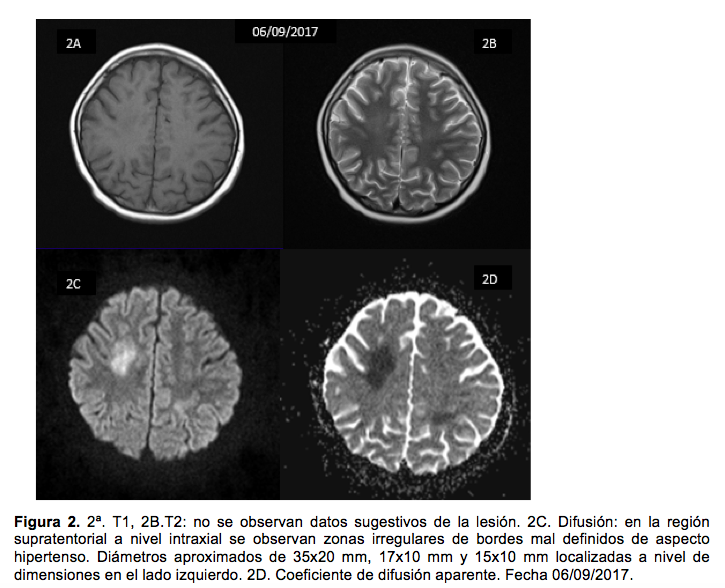

Al octavo día se realizó resonancia magnética de cráneo (figura 2), cuyos hallazgos, sumados a la clínica, sugirieron neurotoxicidad subaguda por altas dosis de MTX. Se comentó con los padres sobre los riesgos y los beneficios del tratamiento con DXM para este tipo de neurointoxicación, quienes aceptaron el uso del fármaco. Por lo tanto, se inició tratamiento con DXM (3 mg/kg/día IV dividido en dos dosis), difenilhidantoína (10 mg/kg/d IV dividido en tres dosis) y ácido acetilsalicílico (100 mg/día VO en una vez cada 24 horas).

Al vigésimo día se pidió resonancia magnética de control, que mostró mejoría en comparación a los hallazgos de la primera (figura 3).